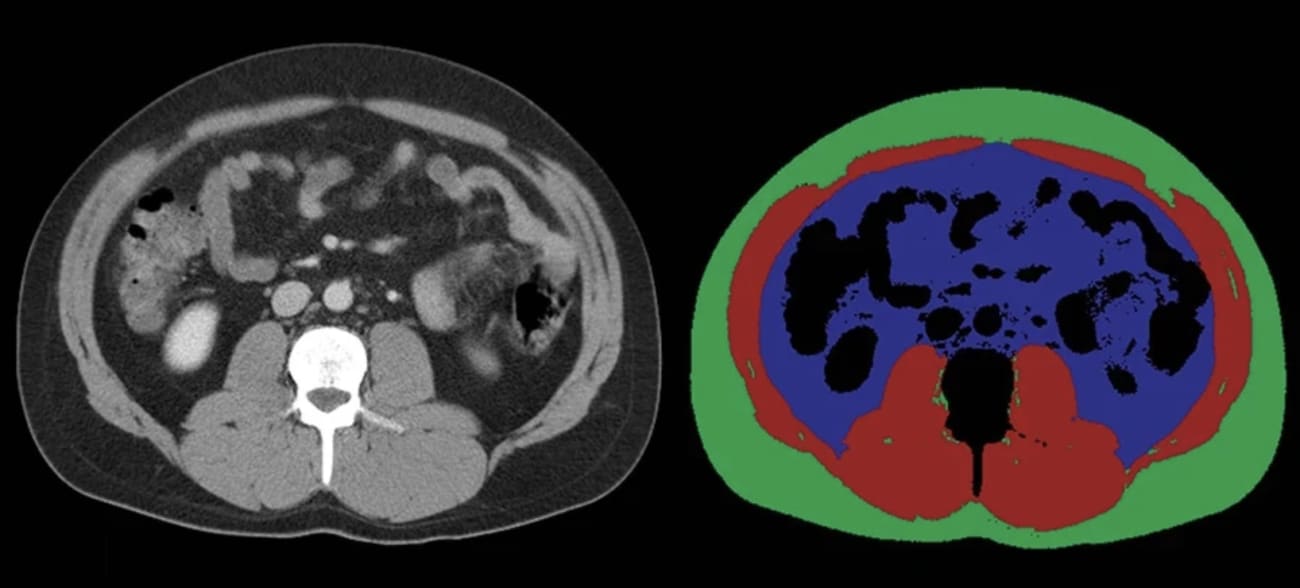

The research is in progress and has so far included the development of an AI model that reads CT scans to assess loss of muscle mass. That tool has enabled the team to determine that muscle mass loss often precedes a pancreatic cancer diagnosis.

AI technology is analyzing CT scans like those pictured here to detect loss of muscle mass, which may be a warning sign of pancreatic cancer.